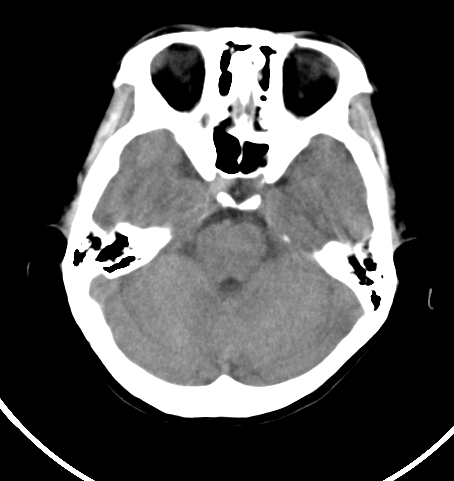

病人女 35岁 自述头晕 头痛

双侧基底节区及右侧丘脑区多发点状钙化,周围未见水肿及占位征象.余未见明显异常.考虑:脑囊虫病<囊虫的退变或死亡期>请结合有无相关病史.

以下是引用苯小孩在2007-4-20 15:47:00的发言:[br]双侧基底节区及右侧丘脑区多发点状钙化,周围未见水肿及占位征象.余未见明显异常.考虑:脑囊虫病<囊虫的退变或死亡期>请结合有无相关病史.

颅内有散在钙化

脑囊虫病理性钙化。